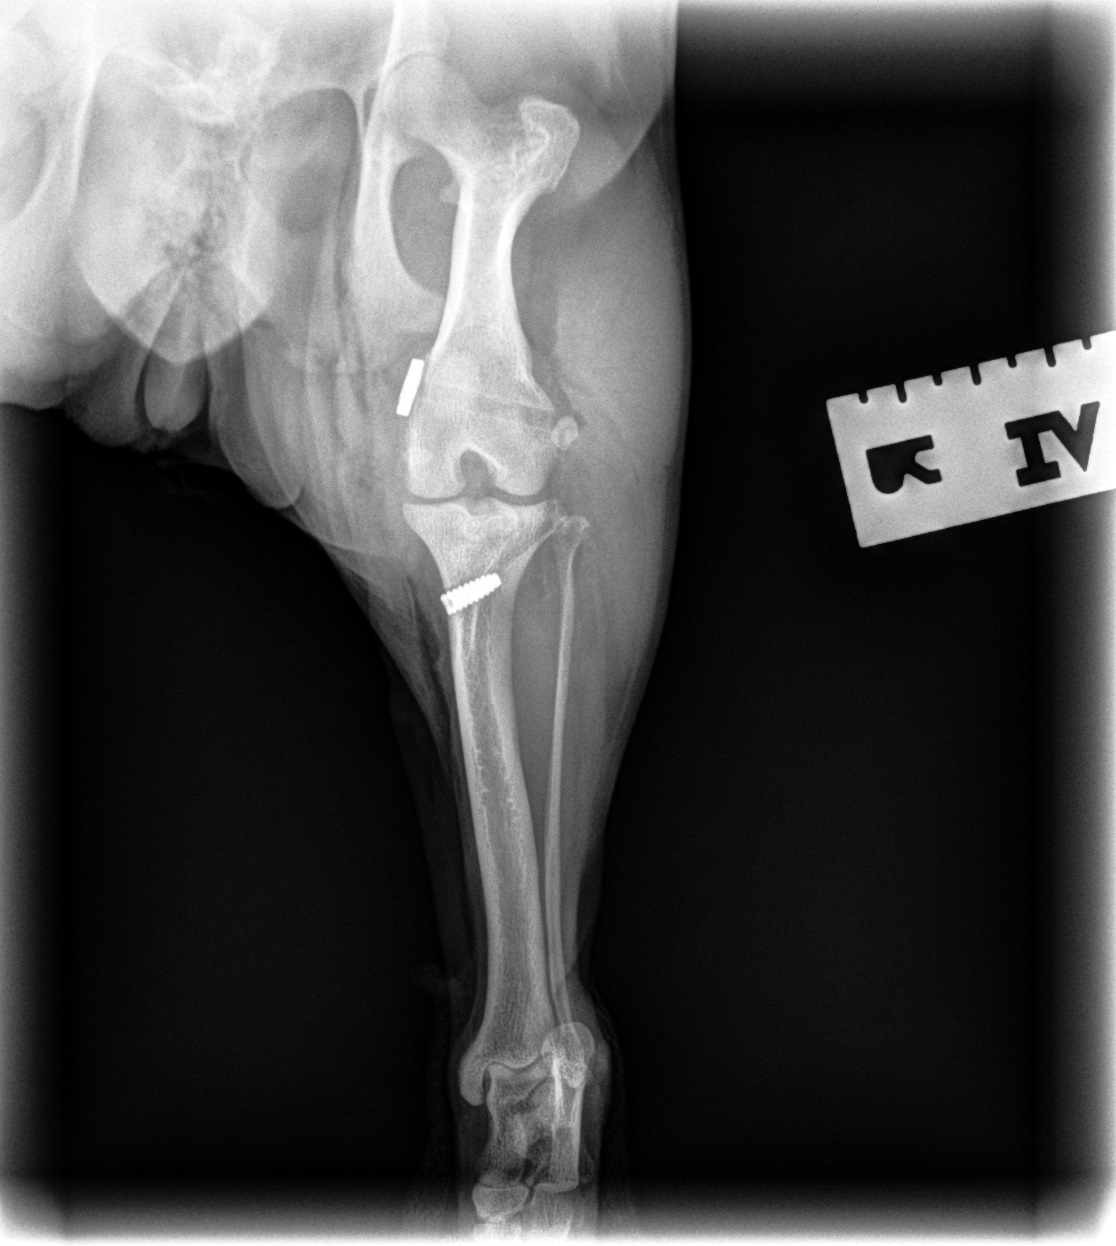

Medial Luxating Patella (MLP) Surgery

A luxating patella occurs when the kneecap moves out of its normal position, which can cause intermittent lameness or long-term joint damage. Surgical correction is available when indicated and is tailored to the severity of the condition and your pet’s clinical signs.

Medial Patellar Luxation (MPL) Repair

Medial Patellar Luxation (MPL) with Extracapsular Repair